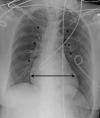

Tetralogy of Fallot (TOF) is a heterogeneous congenital heart disease that is occasionally diagnosed during adulthood. However, although they are often asymptomatic, adult patients with uncorrected TOF often have a poor prognosis. Poor outcomes indicate the importance of the identification and management of these patients, especially in the context of intercurrent disease or noncardiac surgery. We describe a case of clinically silent TOF in a 51-year-old woman. TOF was unmasked during a major noncardiac surgery for a polytrauma and successfully treated with the cooperation of a multidisciplinary team. (Level of Difficulty: Advanced.).